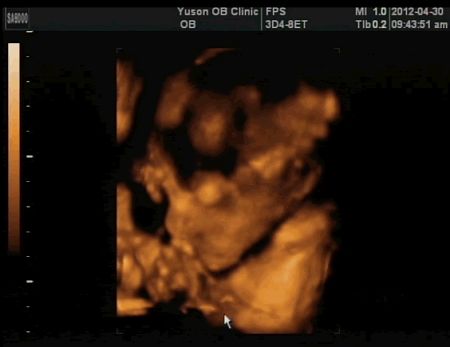

今天醫生拍了很多4D超音波給我看,哈哈!

我發現我兒子很愛做這種沉思的表情

每次照超音波他都會來一個這樣的破似,不過醫生還是又猛搖我的肚子一陣,要他換個姿勢再來一次!